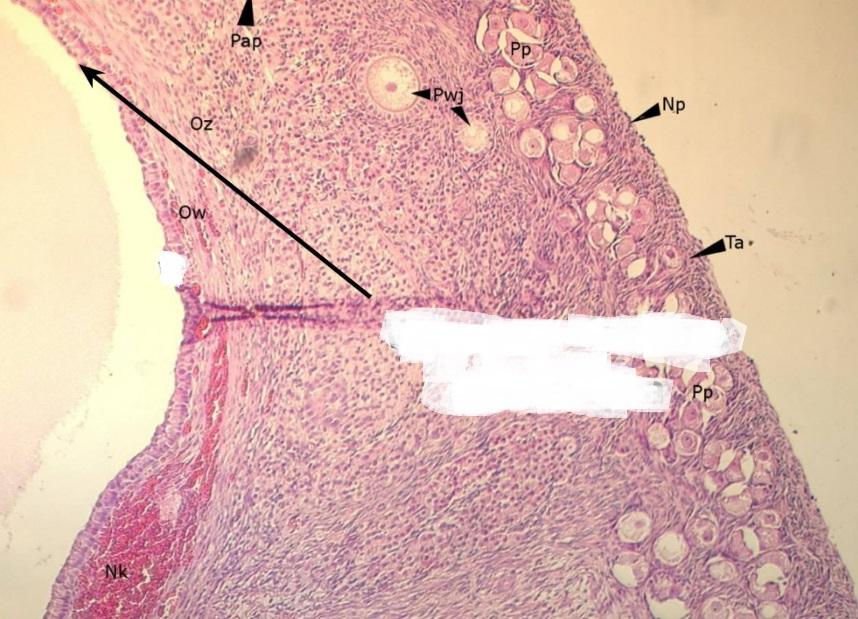

nabłonek sześcienny - płciowy (jajnik, kora)

Pytanie 470

pęcherzyk jajnikowy pierwotny (jajnik, kora)

Pytanie 471

pęcherzyk wzrastający bezjamisty (jajnik, kora)

Pytanie 472

pęcherzyki dojrzewające jamiste (jajnik, kora)

Pytanie 473

pęcherzyk Graafa (jajnik, kora)

Pytanie 474

pęcherzyk atrezyjny (jajnik, kora)

Pytanie 475

błona biaława (jajnik, kora)

Pytanie 476

gruczoły śródmiąższowe (jajnik, kora)

Pytanie 477

warstwa ziarnista pęcherzyka (jajnik, kora)

Pytanie 478

osłonka wewnętrzna - obfita w komórki (jajnik, kora)

Pytanie 479

osłonka zewnętrzna - z dużą ilością włókien (jajnik, kora)

Pytanie 480